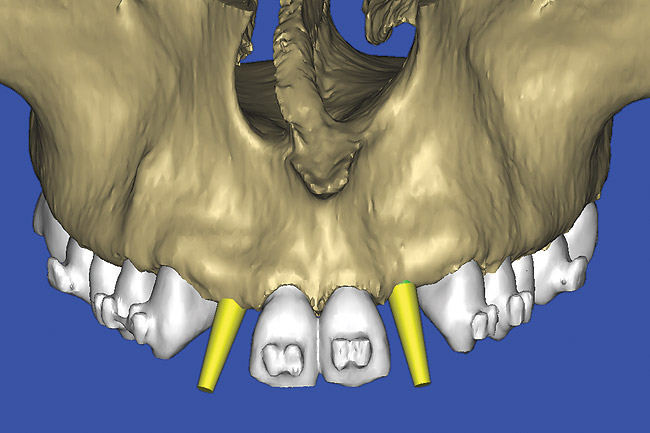

After the basic plan had been established, it was re-evaluated using interactive 3D images. The reconstructed 3D view of the maxilla clearly illustrated the extent of the bilateral facial concavities, and the root eminences of the adjacent and posterior teeth (Figure 12). The placement of the virtual implants then was evaluated to ensure that the facial cortical plate was not perforated (Figure 13). The implants were labeled individually as “7” and “10,” with the simulated yellow abutment projection indicating the facial-lingual inclination through the bone to the level above the incisal edge of adjacent teeth. The ability to gain a better understanding of these individual root forms cannot be underestimated. The dental literature has suggested certain parameters for placing implants near teeth and implants next to other implants. However, there is little scientific 3D documentation to support these suggested rules.5-10 The use of an interactive treatment-planning software application permits closer scrutiny of previously difficult-to-visualize areas, and can now be used to redefine perceptions of spatial positioning of implants, especially when in close proximity to natural tooth roots, vital anatomy, and adjacent implants.27-29

Figure 12  SOFTWARE IMAGING The 3D reconstruction showed the facial concavities and root eminences.

Figure 12

Figure 13  SOFTWARE IMAGING This allowed for evaluation of virtual implant placement to ensure the facial cortical plate was not perforated.

Figure 13